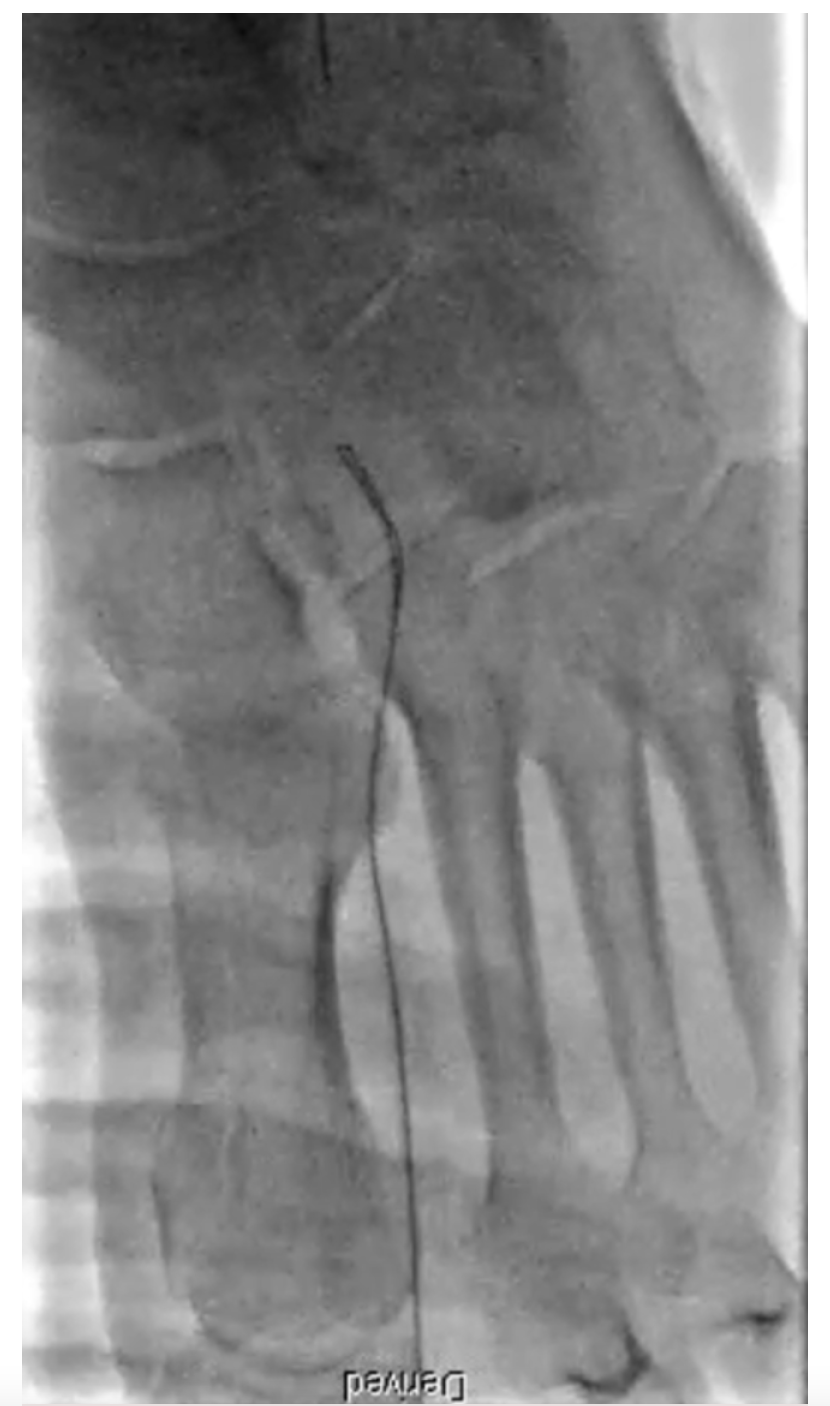

Upon angiographic evaluation, we can assess the pedal arch disease burden and further classify it based on the patency of the anterior or posterior circulation.13 Two views should be performed in all cases using digital subtraction angiography with prolonged imaging to allow late collateral filling. In the lateral oblique view, the fifth metatarsal bone must be separated to properly visualize the common plantar artery and its bifurcation, the dorsalis pedis, and its connection to the pedal arch via the deep perforating artery (Figure 1).21 The anterior-posterior view is also required to visualize the anterior pedal arch vessels directly and evaluate the distal branches into the foot and toes.21 This is essential for visualization of the transmetatarsal artery access required for access in complex cases of CLTI (Figure 2).22

If antegrade wire escalation fails, a retrograde true lumen crossing approach could be attempted. Again, operator familiarity with wiring and wire escalation is essential. If the stenosis is not crossed, a possible controlled antegrade and retrograde tracking approach would be another option. A retrograde approach through the distal transmetatarsal access could be pursued with challenging cases (Figure 4).

In Figure 5 and Figure 6 we illustrate a case where PAR was performed and the arch was utilized for a retrograde crossing of a flush occlusion of the posterior tibial artery. The patient in our case was referred for CLTI with nonhealing wounds in the toes and heel. The anterior tibial artery was recanalized during the initial procedure using laser atherectomy and angioplasty. Then using an antegrade approach, the anterior tibial artery was wired into the dorsalis pedis, across the arch, and retrograde up the posterior tibial artery into the tibioperoneal trunk and externalized in the popliteal artery. This allowed for recanalization of the anterior and posterior tibial artery with a complete plantar arch on the final angiogram, leading to wound healing.